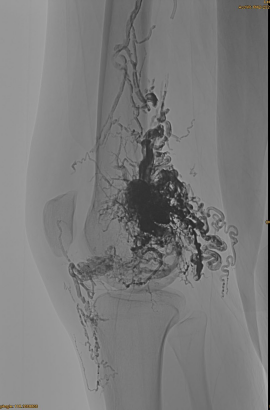

Informații de bază ale pacientului: femeie, 36 de ani; AVM pelvis, șold, genunchi, OSG stânga, multiple pre - embolizări.

Produse utilizate: 3pcs Lava-34,14 pcs Lava-18.

Rezultat final:

Aproape orice flux venos:

Faza târzie, un alt embo necesar, dar mult mai bine: